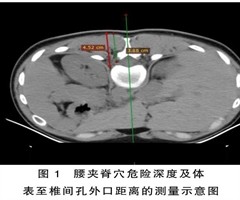

“醒脑通督”针法中腰夹脊穴针刺安全深度的研究

摘要目的:通过螺旋CT平扫技术测量腰夹脊穴针刺危险深度、安全深度及体表到椎间孔外口的距离。方法:选取2020年12月—2021年10月于山西省针灸医院放射科检查的体质指数(BMI)为(18.5~29.5)kg/㎡的成年志愿者54名作为研究对...